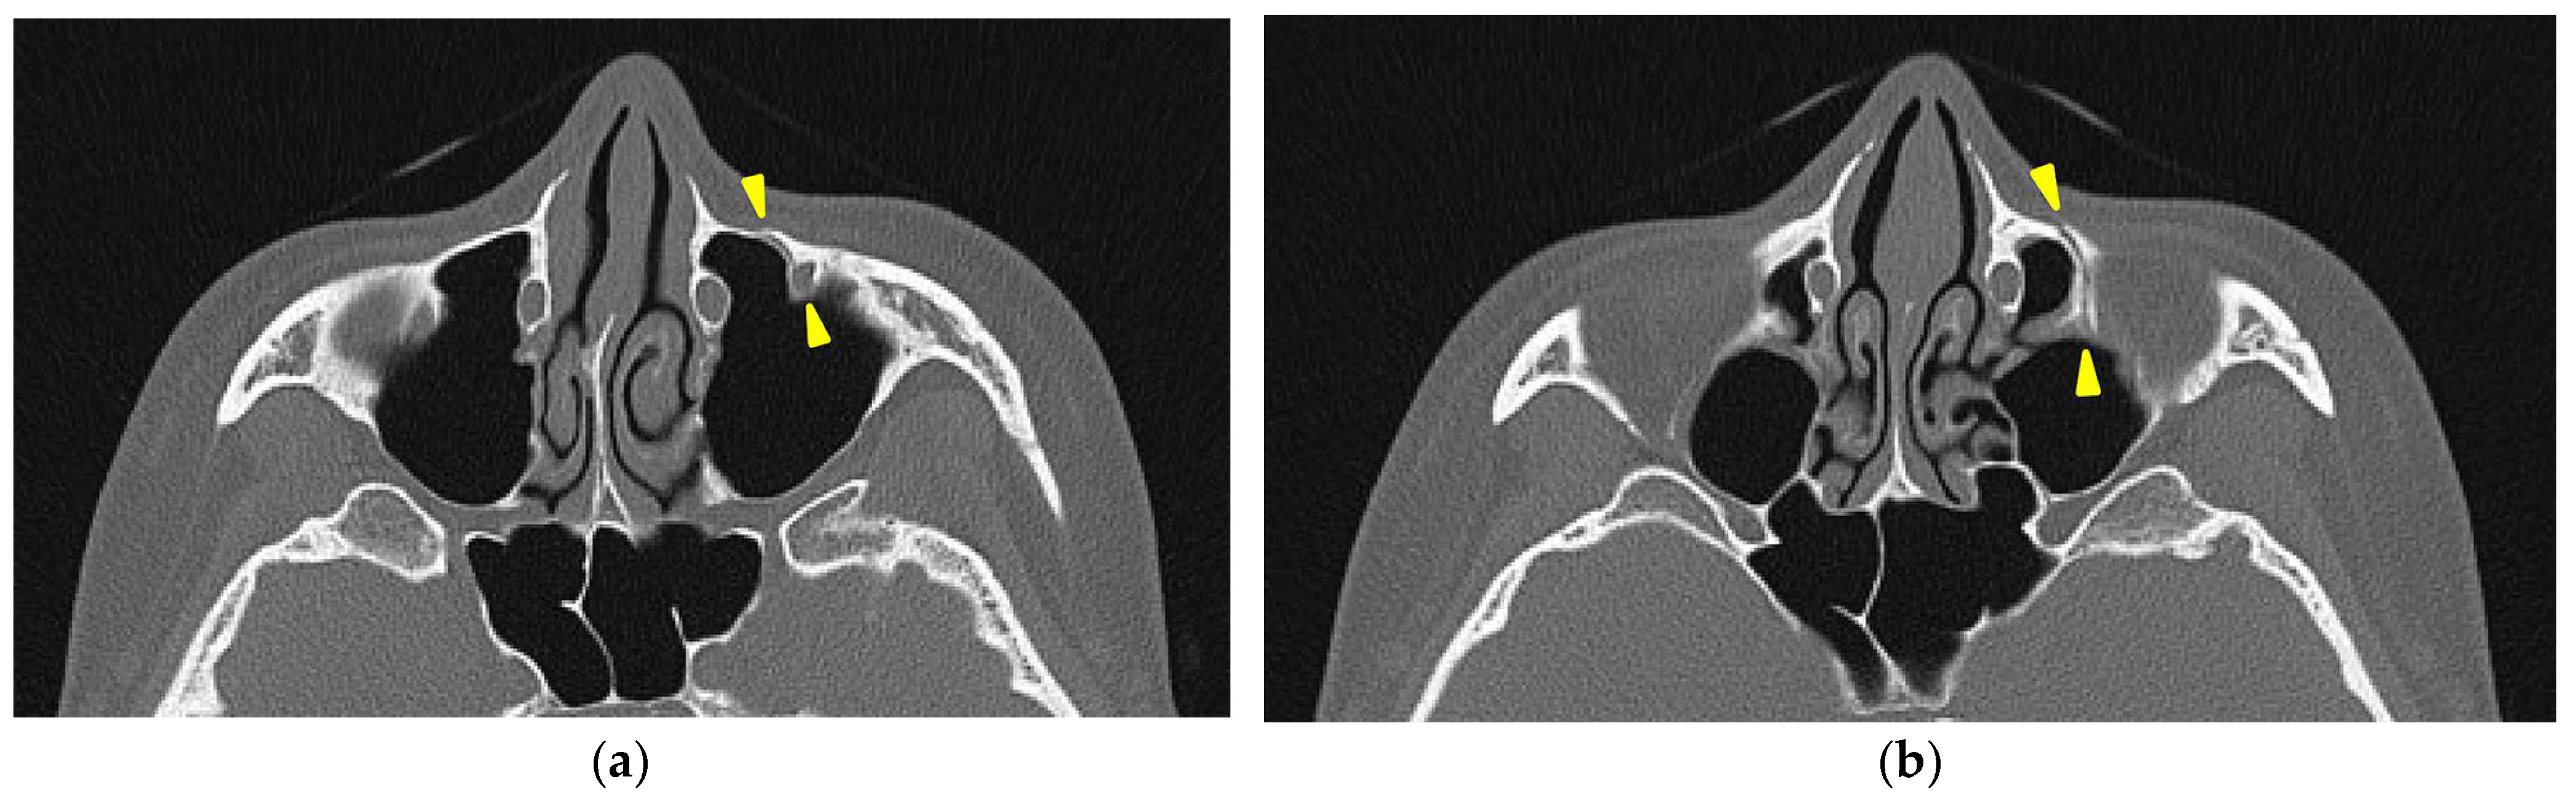

Figure 3). A fracture of the left maxilla was also observed. The line of this fracture extended from the orbital floor and the anterior surface of the maxilla (

Figure 4), starting at the medial edge of the orbital rim, passing through the entire wall of the infraorbital foramen (

Figure 5a,b), and reaching the maxilla’s alveolar process.

The trigeminal nerve sensory disturbances observed in this case were likely caused by a fracture within the infraorbital canal and infraorbital foramen, resulting in nerve injury. This is supported by the fact that the symptoms were limited to the region innervated by the infraorbital nerve. The preservation of maxillary molar sensation indicates that the middle superior alveolar branch, which branches off before the infraorbital canal, was not damaged.

In this case, the fracture was concentrated around the zygomatico-maxillary suture for reasons that are unclear; however, there are studies investigating the correlation between the ossification state of facial bone sutures and the effects of rapid maxillary expansion (RME) devices. Provatidis et al. [

11] analyzed the effects of RME on the craniofacial complex using finite element modeling, a computer simulation method, by applying RME to a dry human skull. Their analysis revealed that while the lacrimo-maxillary, fronto-maxillary, and naso-maxillary sutures had little influence on RME outcomes, the zygomatico-maxillary suture was significantly affected. In this case, three-dimensional CT reconstruction confirmed that the maxillary expansion was resisted by the surrounding bones, particularly the zygomatic bones, leading to the observed fracture. This finding suggests that, unlike in SARPE, where osteotomies reduce skeletal resistance, MARPE encounters direct resistance from surrounding craniofacial structures. Consequently, stress is concentrated at certain anatomical sites, potentially increasing fracture risk. This observation aligns with the finite element analysis by Provatidis et al., which demonstrated that the zygomatic bones serve as the primary limitation to maxillary expansion rather than the nasal or frontal bones. The presence of a fracture in the infraorbital region further supports this idea, as trauma-induced zygomatic fractures frequently involve fracture lines passing through the infraorbital foramen, leading to sensory disturbances similar to those observed in this case. Previous studies on trauma-induced zygomatic fractures have reported that fracture lines frequently pass through the infraorbital foramen, leading to sensory disturbances of the second branch of the trigeminal nerve, which are typical symptoms of such fractures [

13]. The presence of a fracture in the infraorbital region in this case suggests that a similar mechanism may have contributed to MARPE-induced fractures, as the infraorbital foramen is inherently a site prone to fractures caused by external forces.